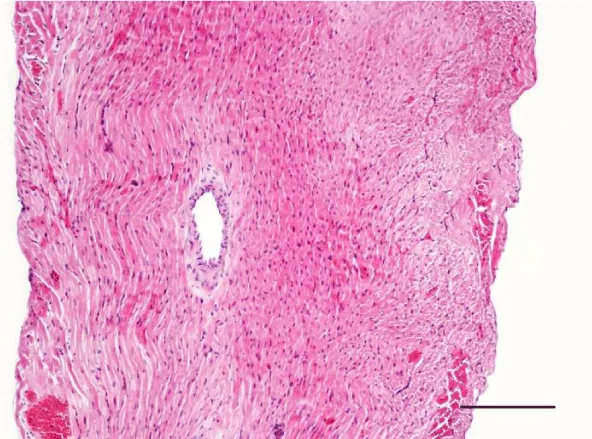

On H&E stained slides in 2-week-old rats, it was difficult to observe clearly defined longitudinal and transverse layers of cardiomyocytes in the wall of the left as well as the right ventricle. Cardiomyocytes appeared to be slightly eosinophilic and pronounced cross striation was not observed. They usually had one centrally located basophilic nucleus; in some cells, one or more nucleoli were noted. The perinuclear zone was well seen and was stained less intensively. The muscle fibers were enveloped by fairly thin connective tissue and a perimysium with abundant capillary network. It was fairly rare that fibroblastic nuclei were observed among the cardiac muscle cells (Figures 1,2).